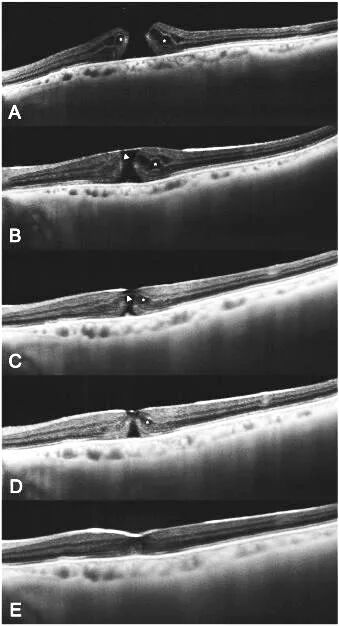

图1 黄斑裂孔ILM瓣翻转覆盖术后即时全域扫频OCT影像。A. 术前全层黄斑裂孔,可见少量前膜,孔缘上翘,伴层间囊样水肿。 B. 玻切术后5分钟,清晰可见气液平面(箭头)下覆盖裂孔的ILM瓣(三角标)。C. 术后1小时,裂孔孔径显著缩小,气液平面(箭头)下可见ILM瓣在位(三角标)。

图2 全域扫频OCT下黄斑裂孔ILM瓣翻转覆盖术后早期形态学愈合过程。A. 术前。B. 术后5分钟即可观察气液平面下ILM瓣(三角标)和裂孔情况。C. 术后俯卧位1h后,即观察到孔径显著减小。D. 术后俯卧位24h后,内层视网膜即已闭合。E. 术后俯卧位48h后,全层裂孔达到解剖学闭合,层间囊样水肿缓解。